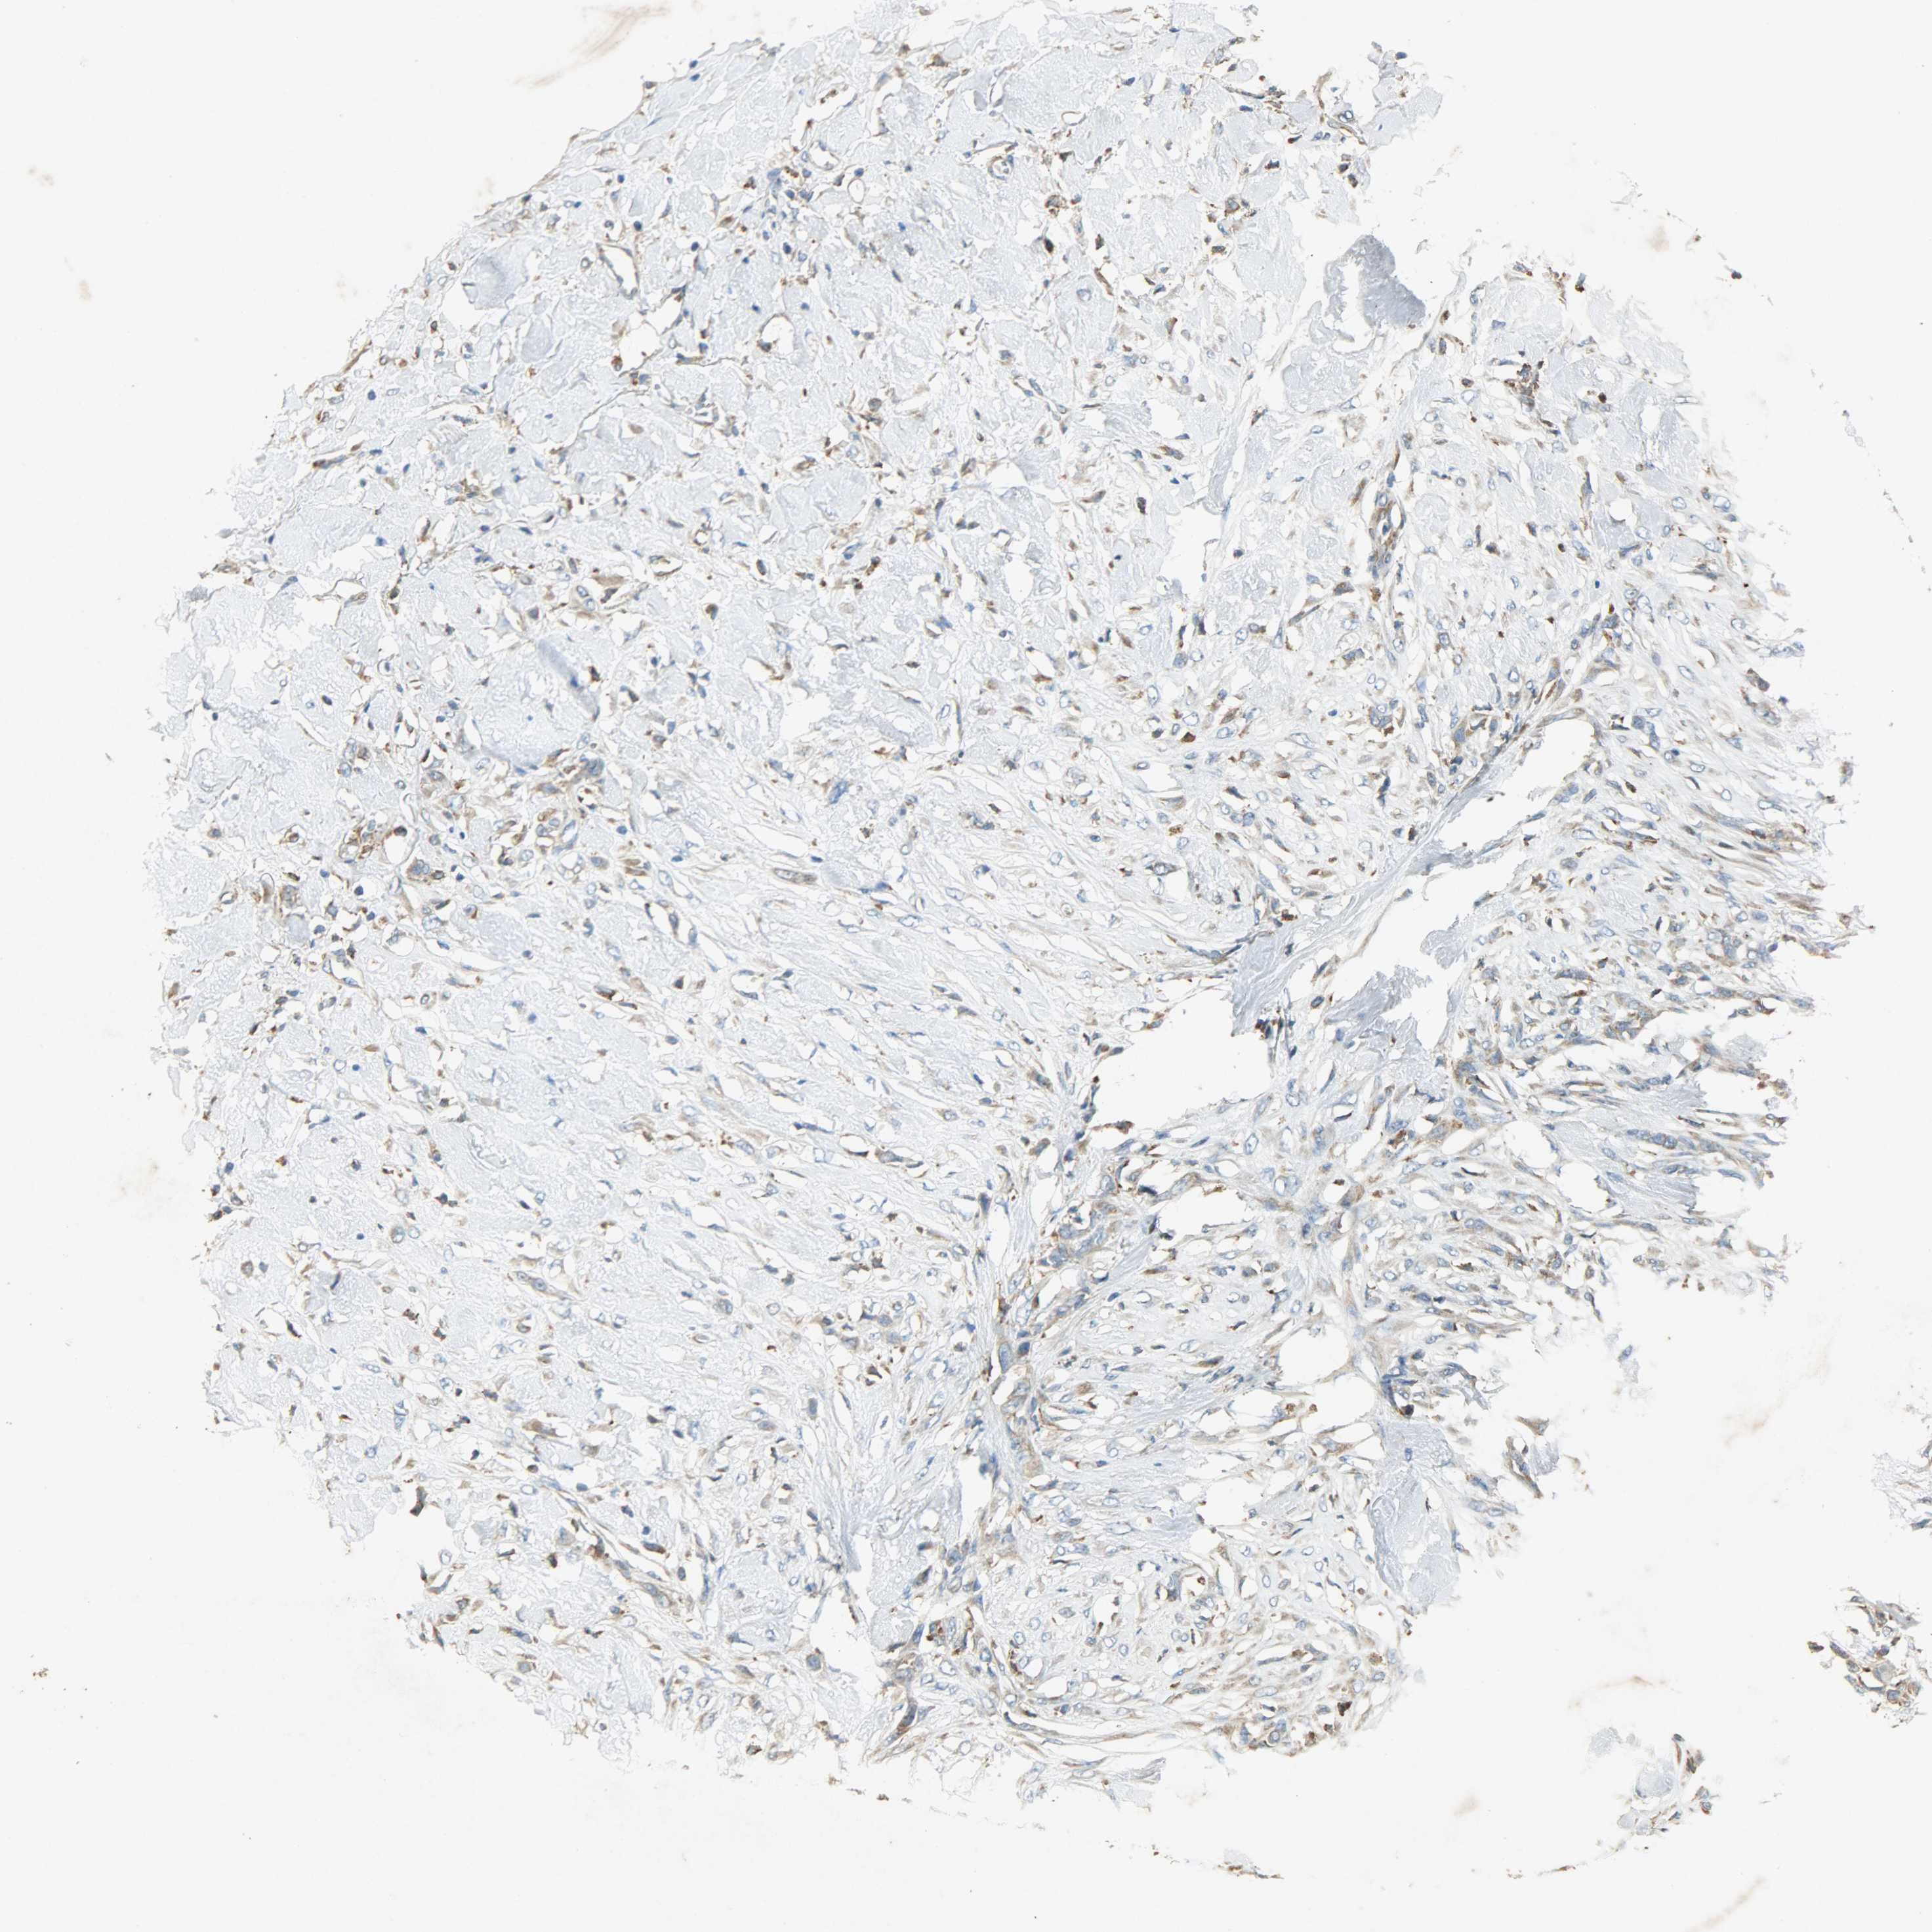

Antibody HPA038845

Basal cell carcinoma